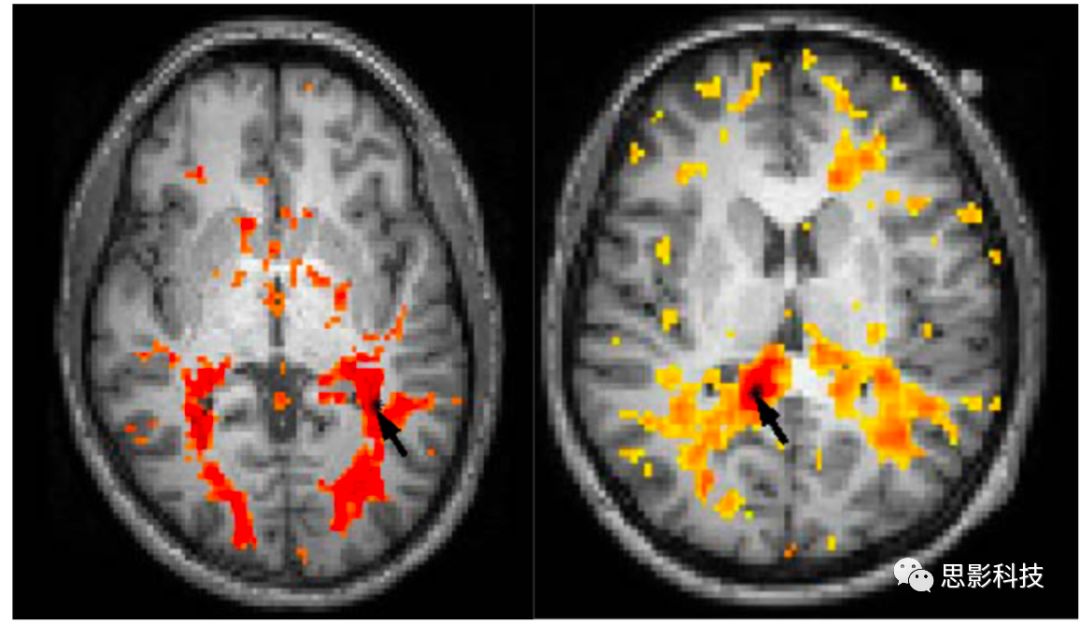

實驗證明,通過誘導血管舒張和降低血液中脫氧血紅蛋白水平可在白質中產(chǎn)生BOLD效應。例如,圖1顯示了容許性高碳酸血癥(指在治療呼吸系統(tǒng)疾病如支氣管哮喘時允許CO2在一定范圍內升高,以避免大潮氣量、過度通氣引起的肺損傷。指在治療呼吸系統(tǒng)疾病如支氣管哮喘時允許CO2在一定范圍內升高,有利于低氧血癥的糾正)對人類機體的影響,結果表明WMBOLD信號強度大約是GM54%,并且需要更長的時間達到峰值。由此可以推斷,與GM相似,含氧血灌注的增加將改變WMBOLD信號。此外,在靜息態(tài)下,在低頻范圍0.01-0.1 Hz可明顯的探測到WMBOLD信號,該特征也被用于皮層的功能連接中。

Fig 1  3 T掃描中,正常人的GM(左)和WM(右)對高碳酸血癥激發(fā)的BOLD反應。WM的作用低于GM,并且需要更長的時間。